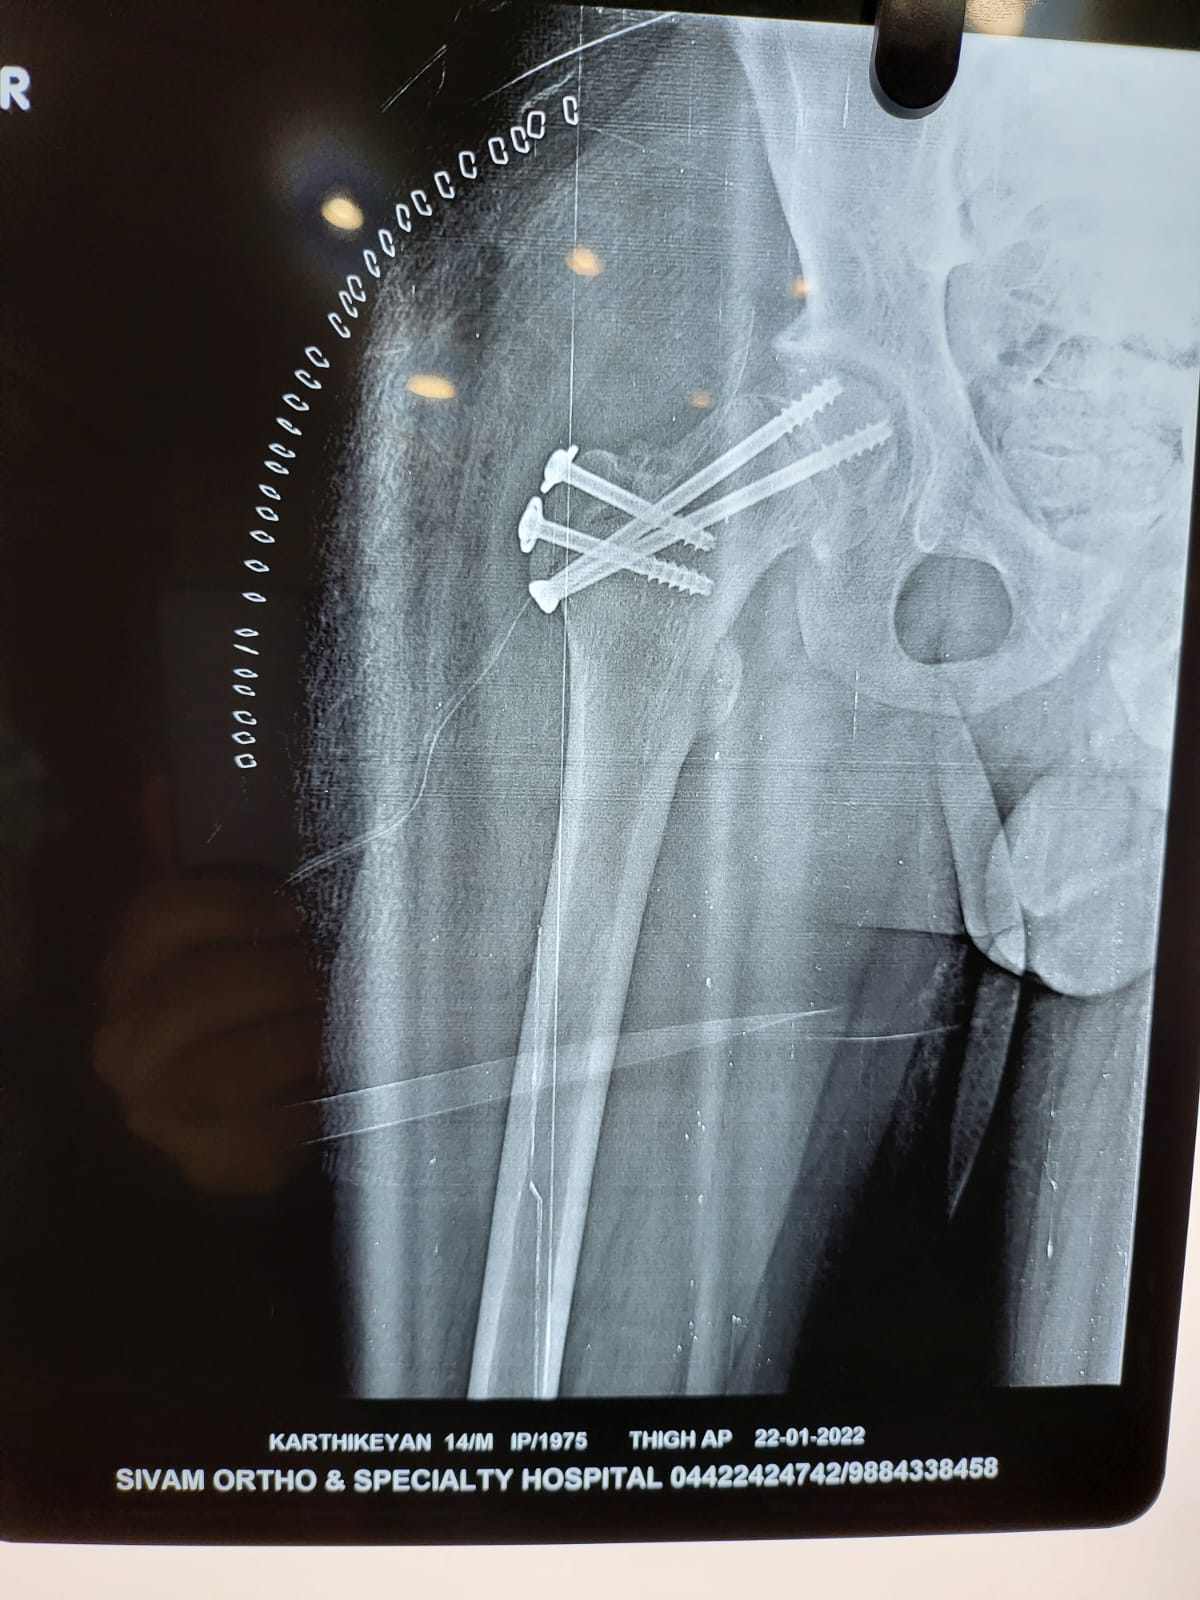

Sivam Hospital – Advanced Hip

Replacement In Chennai

At Sivam Hospital, we specialize in geriatric orthopedics, providing comprehensive care for bone and joint problems in elderly patients. Our orthopedic experts focus on treating age-related conditions such as fractures, arthritis, osteoporosis, and joint degeneration with safe and effective techniques.

We deliver personalized treatment from diagnosis to rehabilitation, making Sivam Hospital a trusted choice for elderly orthopedic care. With advanced facilities, minimally invasive options, and dedicated physiotherapy support, we ensure better mobility, reduced pain, and improved quality of life for senior patients.

Expertise in Fracture Management, Arthritis & Osteoporosis Care

Specialized Joint Replacement & Trauma Care for Seniors

Modern Operation Theatres & Imaging Support

Compassionate Elderly-focused Rehabilitation & Physiotherapy

Safe, Reliable & Patient-Centered Orthopedic Care

Walk without pain. Trust Sivam Hospital for advanced hip replacement and a better quality of life.